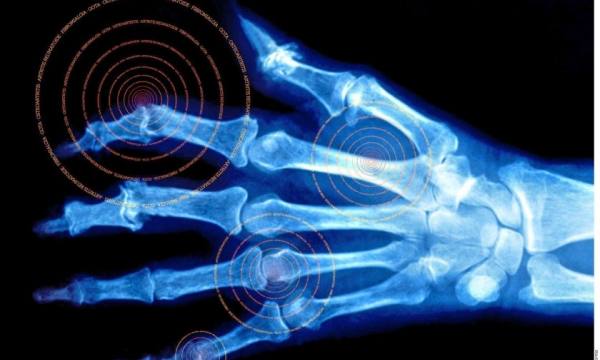

REUMA es una palabra que no fija ni aclara acerca de ninguna enfermedad reumática, por lo tanto, lo primero es aclarar que actualmente existen más de 250 enfermedades clasificadas y claramente definidas conocidas y con rigor científico.

Si bien es cierto que las manifestaciones clínicas más habituales de presentación refieren al dolor e inflamación articular, o dolor óseo localizado, acompañado de algún grado de limitación a los movimientos, debo dejar muy en claro que la reumatología es una sub-especialidad de la clínica médica, y como tal existen formas de presentación de las enfermedades con afectación de órganos y sistemas muy disimiles, tales como, corazón, pulmón, piel, vasos sanguíneos, manifestaciones oculares, renales, cerebrales, etc., por ello de la importancia del conocimiento clínico, la interconsulta a tiempo y el trabajo en conjunto con las restantes especialidades médicas.